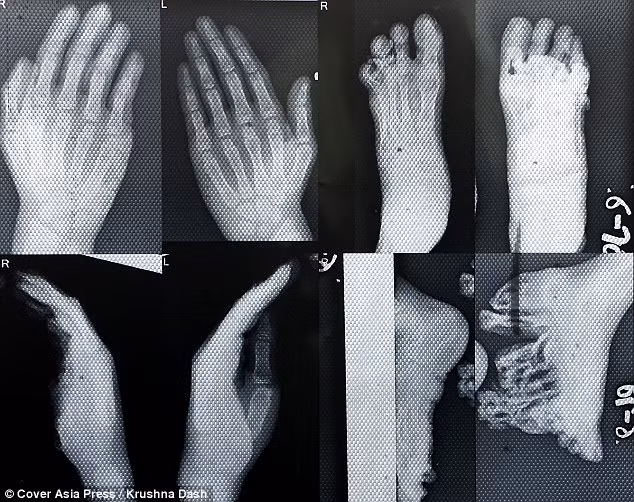

(Kiến Thức) - 3 chị em người Ấn Độ này đều mắc bệnh lạ, bàn chân da mọc dày và nở tung tóe khiến chúng không thể đi lại bình thường được.

Bé Gitarani Sethi, 12 tuổi và 2 em sinh đôi Ganga và Jamuna, 6 tuổi sống tại Bhadrak, ở Orissa, miền đông Ấn Độ đều mắc phải hội chứng Olmsted, căn bệnh khiến da dày lên bất thường ở lòng bàn tay và lòng bàn chân.

Điều đáng nói là, khi sinh ra các bé đều khỏe mạnh bình thường, cho đến khi 1 tuổi, chứng bệnh lạ này mới bùng phát, gây nên những u cục đau đớn ở lòng bàn chân, khiến chúng không thể mang giày dép và không thể đi lại, chạy nhảy bình thường như những đứa trẻ khác.